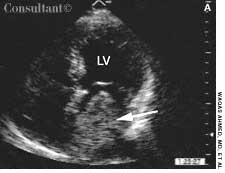

A 56-year-old man who had hematuria for 2 weeks underwent ultrasonography. This disclosed a well-circumscribed cyst in the lower pole of the left kidney and echogenic foci in the upper pole of the right kidney, without any evidence of posterior shadowing. A hyperechoic, well-circumscribed, circular focus was also seen in the right lobe of the liver. Abdominal CT confirmed the presence of a left renal cyst and revealed a 4.7-cm hypodense lesion in the right lobe of the liver, which suggested hemangioma.